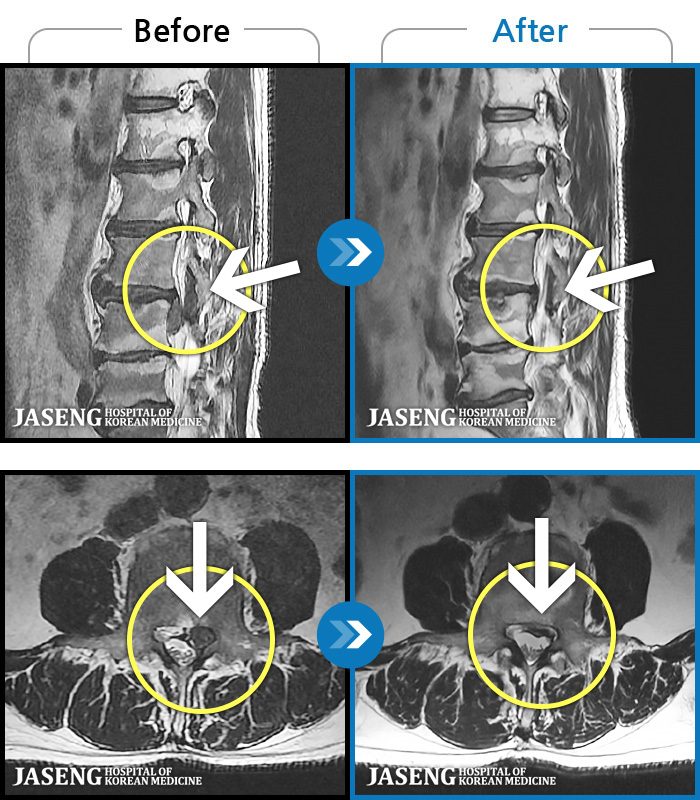

- MRI ġ

MRI ġ

1,240 MRI ũ ʸ Ȯϼ.